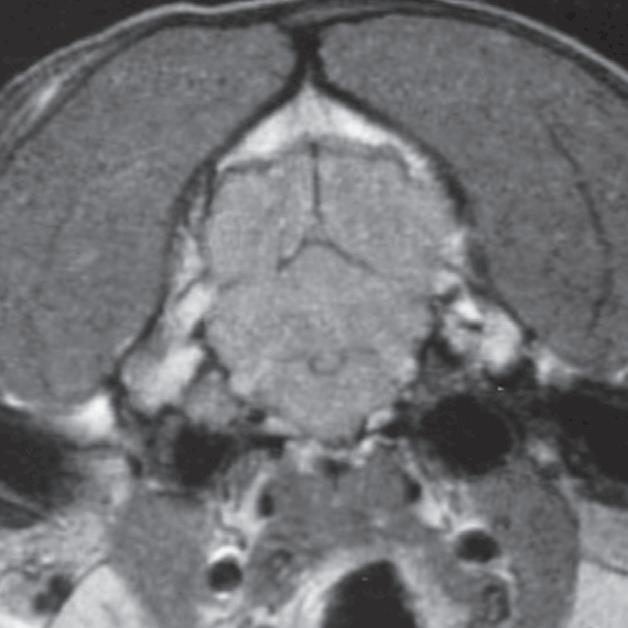

U 6-letniego samca rasy rhodesian ridgeback od 4 dni obserwowano objawy wskazujące na chorobę móżdżku. Stwierdzono słabo odgraniczony, izointensywny w T1 i hiperintensywny w T2 obszar w robaku i lewej półkuli móżdżku (a, b – groty strzałek), któremu nie towarzyszył żaden znaczący efekt masy. Po podaniu kontrastu nie zobrazowano wzmocnienia zmiany. Test immunofluorescencji pośredniej (IFA) wykazał miano zgodne z aktywnym zakażeniem Neospora. Badanie pośmiertne wykonane ok. 3 miesięcy po wstępnym rozpoznaniu potwierdziło martwicze, ziarniniakowe zapalenie móżdżku z pierwotniakami odpowiadającymi Neospora wewnątrz ognisk